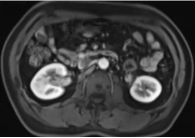

(2)下腹部增强核磁:显示右侧肾盂增厚,输尿管上段周围软组织增厚、管腔狭窄。